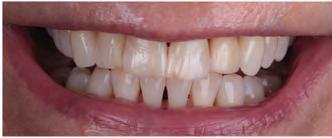

A 31-year-old woman presented with cosmetic concerns regarding her smile and requested a conservative enhancement. After clinical and radiographic analysis, digital 35mm photographs were taken and reviewed by the restorative clinician, technician, and surgeon (Fig 1). A digital impression was taken of the maxillary and mandibular arches using an intraoral scanner (Trios 3, 3Shape; Fig 2), and a smile design was developed with NemoSmile Design 3D software (Nemotec; Fig 3a). This allows for a facially driven smile frame to be created using reference lines of facial and smile proportions and natural teeth shapes and textures from the digital library (Fig 3b).

After developing the simulated mock-up, a 3D-printed resin model was created using CAD software (Fig 4a), and a clear PVS matrix (Exaclear, GC America) was fabricated to replicate the printed diagnostic wax-up using a nonperforated tray (Fig

Fig 1 Preoperative clinical views of a 31-year-old woman presenting with diastemas and limited tooth visibility. (top) Portrait. (center row) Intraoral views. (bottom row) Smile.

4b). This matrix was used to create an intraoral motivational mock-up with bis-acryl composite (Luxatemp Ultra, DMG). This additive mock-up provides the interdisciplinary team with an intraoral translation for evaluation (Fig 5). Upon evaluation of the digital smile frame and the clinical translation, it was determined that multiple esthetic and restorative requirements were necessary for an optimal biologic framework, and the interdisciplinary team determined the best sequence for these procedures. The patient was presented with the interdisciplinary treatment possibilities that included restoring the maxillary anterior teeth and premolars with a minimally

invasive preparationless procedure or with less conservative veneer preparations. The restorative materials discussed included injectable resin composites and ceramic (ie, feldspathic, pressable, machinable). For an optimal biologic framework and health, it was determined that connective tissue grafting would be necessary for treatment of the recessiontype defects on the maxillary left central and lateral incisors, canine, and premolars. The patient opted for the conservative preparationless composite veneers using the injectable resin technique followed by a connective tissue surgical procedure using the tunneling technique.